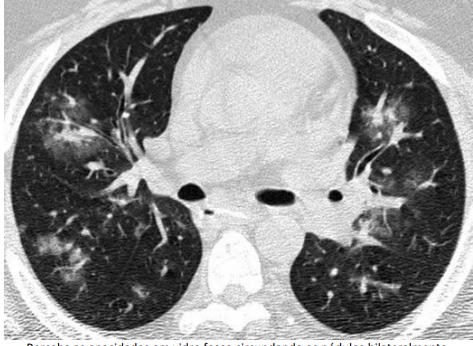

8

Q

Sinais e padrões torácicos

Qual padrão da imagem?

A

Padrão de árvore em brotamento

* Perceba que poupa as regiões subpleurais